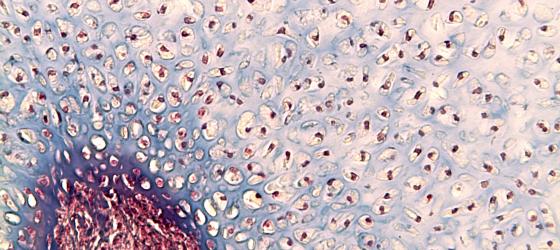

Figure C110A. Human bone marrow in situ at higher magnification

Figure C110A. Human bone marrow in situ at higher magnification. You can clearly see both the endosteum that lines the lamellar bone and some large megakaryocytes inside the hematopoietic tissue. H&E X100

Figura C110B. Midollo osseo umano in situ a più forte ingrandimento

Figure C110B. Human bone marrow in situ at higher magnification. You can clearly see both the endosteum that lines the lamellar bone and some large megakaryocytes inside the hematopoietic tissue. H&E X100

Figura C111. Midollo osseo umano a forte ingrandimento

Figure C111. Human bone marrow at high magnification. You can see islets of hematopoietic tissue mixed with adipocytes. In the center of the micrograph, you can see a large cell with a polylobed nucleus: the megakaryocyte (arrow), from which platelets originate by budding cytoplasm portions. H&E X200